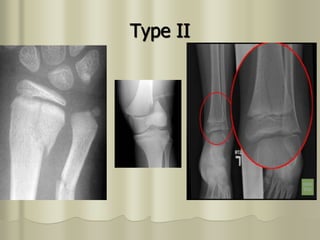

• Most common type and accounts for 75% of

all physeal injuries.

• Transverse fracture through the growth plate and an oblique or vertical

fracture through the metaphysis.

• The type II injury starts as a horizontal separation (like type I) but this is

completed by exiting through the metaphysis, resulting in a triangular

fragment which varies in size.

• This is the most common type of physeal separation and is usually easily

reduced but not always easy to hold reduced, in a cast. Sometimes the torn

periosteum becomes trapped in the fracture site preventing a full reduction

by closed means. The trapped periosteum sometimes needs to be released

by open operation, especially at the ankle.

TypeII

Type II